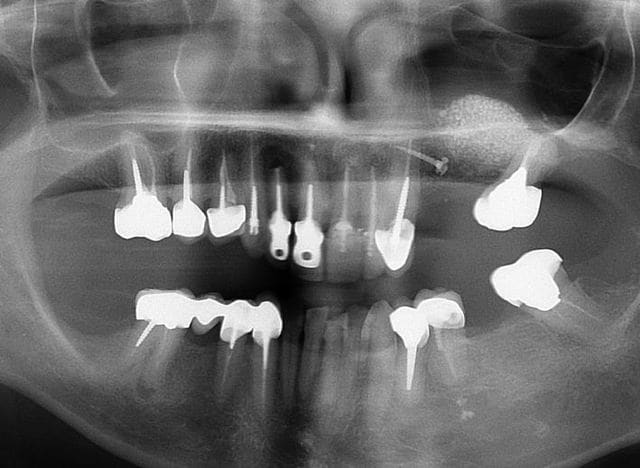

la pano c'est post op ?

Oui c'est bien la pano post op

Image r6habu - Eugenol

Tu es sur que le méat est ouvert de ce coté? on voit pas sur tes images;